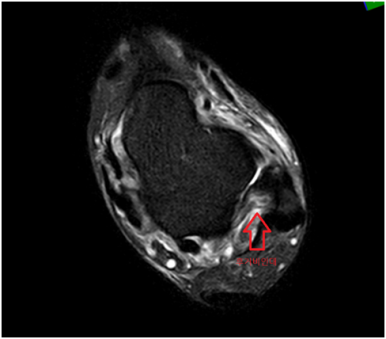

발목 MRI에서 바깥쪽 인대를 구성하는 전거비인대, 후거비인대에 심한 손상, 안쪽 인대를 구성하는 삼각인대 손상, 발목 경비인대결합 손상으로 수술이 가능한 정형외과 병원으로 전원하였습니다.

• MRI 검사: 인대 손상 MRI 검사: 인대 손상